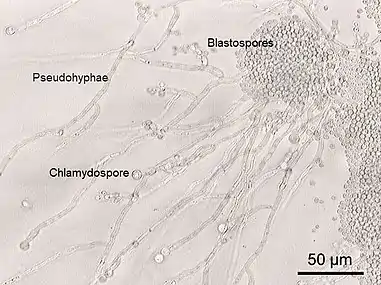

Some yeast species have the ability to develop multicellular characteristics by forming strings of connected budding cells known as pseudohyphae or false hyphae, or quickly evolve into a multicellular cluster with specialised cell organelles function.[5][6] Yeast sizes vary greatly, depending on species and environment, typically measuring 3–4 µm in diameter, although some yeasts can grow to 40 µm in size.[7] Most yeasts reproduce asexually by mitosis, and many do so by the asymmetric division process known as budding. With their single-celled growth habit, yeasts can be contrasted with molds, which grow hyphae. Fungal species that can take both forms (depending on temperature or other conditions) are called dimorphic fungi.

Yeasts of the genus Candida, another group of opportunistic pathogens, cause oral and vaginal infections in humans, known as candidiasis. Candida is commonly found as a commensal yeast in the mucous membranes of humans and other warm-blooded animals. However, sometimes these same strains can become pathogenic. The yeast cells sprout a hyphal outgrowth, which locally penetrates the mucosal membrane, causing irritation and shedding of the tissues.[117] A book from the 1980s listed the pathogenic yeasts of candidiasis in probable descending order of virulence for humans as: C. albicans, C. tropicalis, C. stellatoidea, C. glabrata, C. krusei, C. parapsilosis, C. guilliermondii, C. viswanathii, C. lusitaniae, and Rhodotorula mucilaginosa.[118] Candida glabrata is the second most common Candida pathogen after C. albicans, causing infections of the urogenital tract, and of the bloodstream (candidemia).[119] C. auris has been more recently identified.